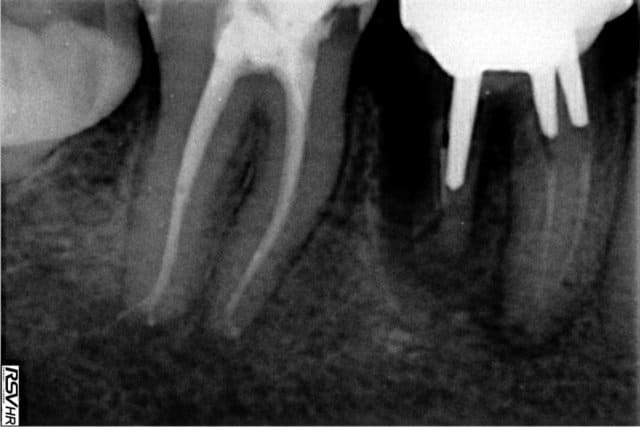

pas mal ceel

mais bon, y a quand même quelques tenons dans l'axe...;-)))

j'adore celui de la 16 qui vient s'ancrer dans la 17...mdr ;-)))

bon, et bien là t'as du taf...;-)

et celui de la 14 en 13....

fortiche le gars